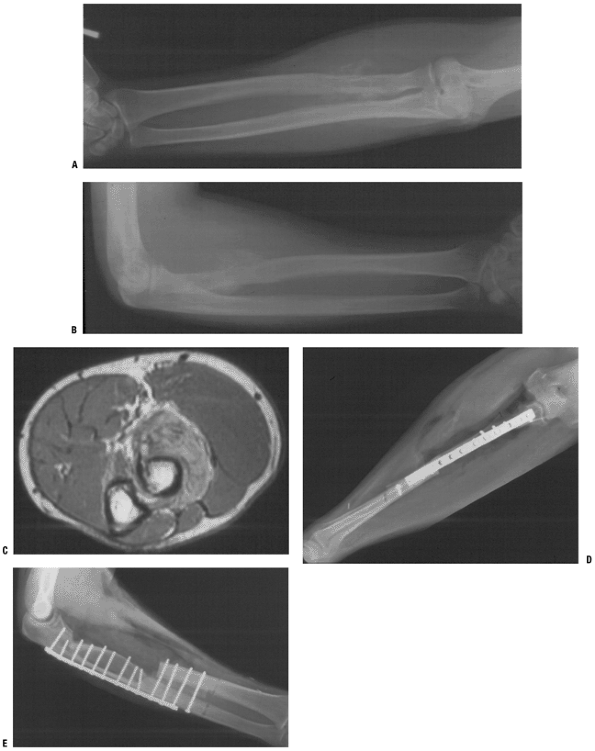

P.69![]() Figure 4.3-10 Figure 4.3-10

Single-bone forearm reconstruction following resection of a proximal

radial osteosarcoma. Preoperative studies include AP and lateral

radiographs (A,B) and an axial T1-weighted magnetic resonance image (C). (D,E) Postoperative AP and lateral radiographs.P.70 Figure 4.3-11 (A,B) Figure 4.3-11 (A,B)